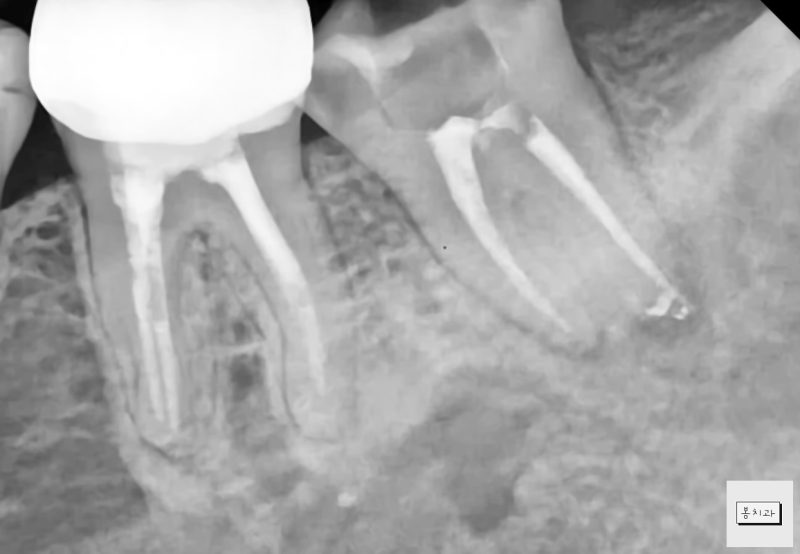

수술 시 걱정 치근을 둘러싼 염증 조직을 충분히 제거했습니다. 염증의 원인이 되는 치근을 절제한 후 밀폐가 쉬운 생체 친화성 시멘트인 mta로 충전했습니다.

술 먹고 한 달 뒤에요.